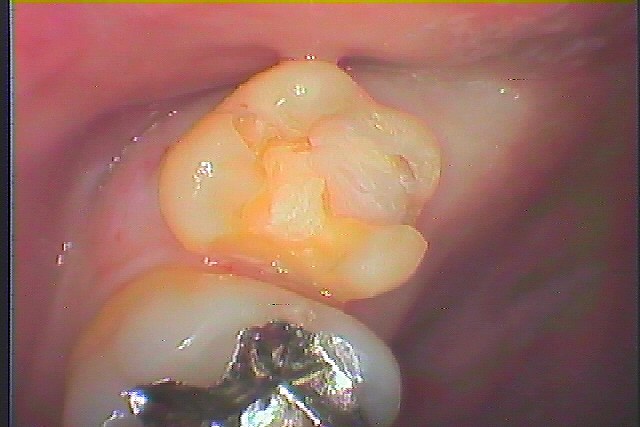

銀歯を外してセラミックを入れていきます 審美治療 40代女性|お知らせ |広島市安佐南区の歯科医院 銀歯を外してセラミックを入れていきます 審美治療 40代女性 トップ お知らせ・ブログ お知らせ 銀歯を外してセラミックを入れていきます 審美治療 40代女性 銀歯を外してセラミックを入れていきます 審美治療 40代女性 この銀歯を外していきます 境眼が黒く虫歯になって生きています 外したところになります CR樹脂にて覆罩を行っていきます セレックセラミックにて綺麗に修復しました 左上7番の銀歯を外していきます 虫歯を除去していきました セレックセラミックにてきれいに修復しています Web診療予約 初めての方へ 選ばれ続ける理由 院内設備について 歯が痛いしみる一般歯科 歯がぐらぐらする歯周病 健康な歯を保ちたい予防歯科 子供の虫歯予防をしたい小児歯科 銀歯をセラミックに審美歯科 白い歯を目指しませんか?ホワイトニング 矯正専門医がいるので安心矯正歯科 抜けた歯を補いたいインプラント・入れ歯 医院案内 スタッフ紹介 メリィハウス歯科クリニックオフィシャルホームページ ラベンダー歯科クリニックオフィシャルホームページ お知らせ・ブログ ホーム 診療科目 一般歯科 歯周病治療 予防治療 小児歯科 審美治療 ホワイトニング 矯正歯科 入れ歯・インプラント マウスピース矯正 初めての方へ 院長・スタッフ 設備紹介 医院案内・アクセス メニューを閉じる